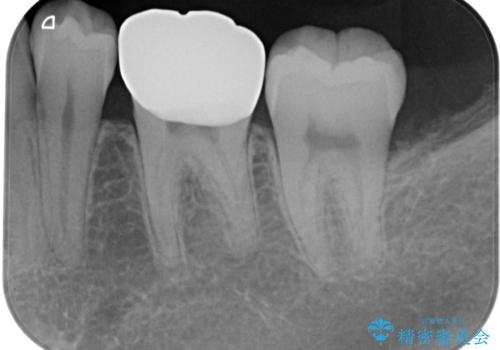

仮歯の状態で1週間ほど過ごしてもらい、しみる症状も改善されたので

歯と歯茎の間に圧排糸と言われる糸を入れてシリコーン印象材にて型どりをしました。

痛みやしみることもなく、適合もよく、機能的に問題もなく、見た目も満足されていました。

今後は他の金属の詰め物(メタルインレー)のところを治療していく予定です。